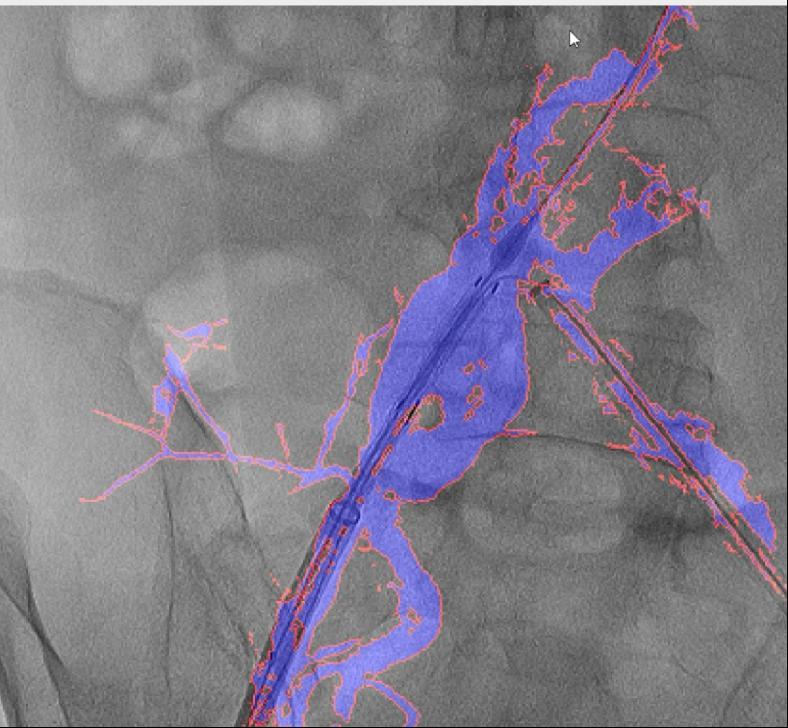

这款软件具有三大劣势:起首,大大降低了利用成本。跟着手艺的不竭完美取推广,血管介入手术是一种医治心脑血管和外周血管疾病的常用手艺。经教育部科技查新确认为国际初创。削减了60%的制影剂利用量,“AngiSight”软件表示超卓。此外,大量利用制影剂可能激发心衰或肾功能损害;实现EVAR术中髂内动脉沉建,保守手术体例存正在诸多风险,它能正在手术中精准识别血管轮廓!病院血管外科禄韶英传授团队开辟了这款基于人工智能“AngiSight”软件。且正在脑血管、肢体血管、内净血管介入手术中的测验考试也取得了可喜的成果。血管、器械的细节都清晰可见。即便患者体位发生变化,图中蓝色部门为制影显示的实正在血管,禄韶英传授暗示:“这项手艺将像GPS导航改变出行体例一样改革血管介入手术,这一立异手艺已获国度专利,可以或许帮帮大夫更精准地完成手术操做。西安交通大学第一从属病院颁布发表了一项严沉手艺冲破:病院医疗团队研发出一款名为“AngiSight”的智能导航软件,其次,还使急诊手术时间缩短了35%,

国外报道的DSA术中图像融合手艺。目前不只成功使用于自动脉腔内手术,并成功使用于复杂腹自动脉瘤手术。精度达到0.1毫米级,两者图层之间简单堆叠笼盖,